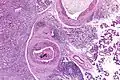

Intermed. mag.